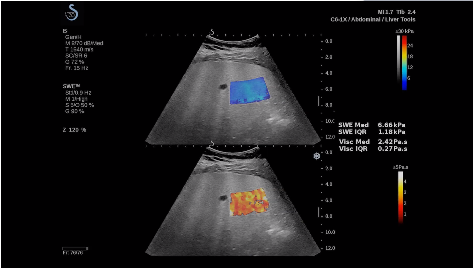

法國(guó)聲科影像(SuperSonic Imagine,SSI. Euroniex:FR0010526814)近日發(fā)表公告,宣布其研發(fā)的新一代“極速”超聲成像平臺(tái)(UltraFast Imaging),首次實(shí)現(xiàn)了肝臟的多項(xiàng)超聲定量評(píng)估新指標(biāo)同步檢測(cè),包括:Att PLUS,SSp PLUS和Vi PLUS等,基本涵蓋肝臟相關(guān)病理變化指征的如纖維化、脂肪變、炎癥等。據(jù)悉,此多項(xiàng)新技術(shù)新將搭載于新Aixplorer系列E超系統(tǒng)。

E超相關(guān)技術(shù)已被多項(xiàng)多中心大樣本研究證實(shí)對(duì)于肝纖維化無(wú)創(chuàng)評(píng)估有重要意義,同時(shí)也可全面應(yīng)用于乳腺、甲狀腺、肝臟、前列腺、肌骨、婦科等全身各組織器官的定量評(píng)估和鑒別診斷。在慢性肝臟方面,聲科E超的肝臟相關(guān)定量診斷技術(shù)集,于2018年獲得美國(guó)FDA認(rèn)證,成為FDA歷史上首次獲批的單病種超聲全面定量解決方案。

E超是在原有B超、彩超(彩色多普勒CDFI)基礎(chǔ)上研發(fā)成功的新一代超聲剪切波彈性成像系統(tǒng),是一種能夠全面應(yīng)用于表淺組織、腹部臟器,血管等方面的組織彈性成像技術(shù)。根據(jù)組織硬度彈性值的不同,有效鑒別實(shí)性腫瘤的良惡性。對(duì)于惡性病變的診斷具有較高的特異性和敏感性,尤其對(duì)于甲狀腺、乳腺、前列腺等小器官,能夠完成常規(guī)超聲不能完成的組織定量分析,可以實(shí)時(shí)、全幅、全定量獲得組織彈性(硬度)信息,為鑒別腫瘤的良惡性提供客觀(guān)、量化的診斷依據(jù)。